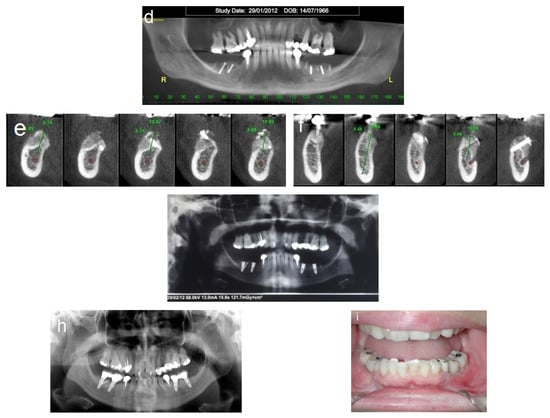

Follow-up was scheduled three times every two weeks, then monthly. Partial exposure of the graft occurred at four weeks on the right side but was successfully managed without compromising the augmentation outcome. A CBCT scan was obtained after four months to assess the bone gain (Figure 4a–c). Dental implants were placed 4 months after the procedure (Figure 4d–i). A fixed prosthesis was delivered four months after the implant placement. This case was followed for 10 years (Figure 5).

Figure 4.

Reentry at 4 months. (a–c) CBCT post-op demonstrating significant horizontal bone gain. (d) Left-side view, showing excellent integration of the bone blocks and the width of the new bone demonstrated by the length of the removed fixation screws (e). (f,g) Placement of three implants on the left side. (h) New bone volume on the right side. (i) Placement of three implants on the right side.

Figure 5.

Follow-up. (a,b) Ten-year follow-up post-loading, showing the implant at the recipient site with no marginal bone loss.